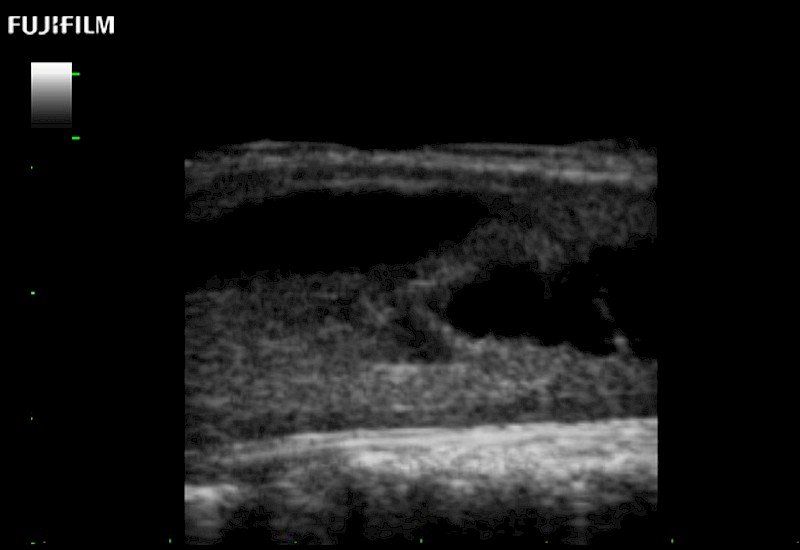

Exclusive 10mm side‐fire linear array transducer with 2.87mm diameter is ideal for real‐time visualization through and behind structures and instant, scalable definition of anatomy and vascularity including the ability to delineate and define tumor margins.